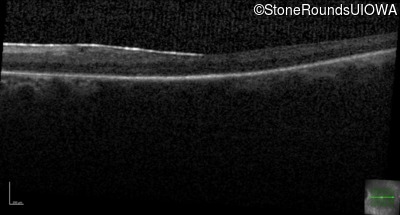

Age at visit: 59 years

OD OS